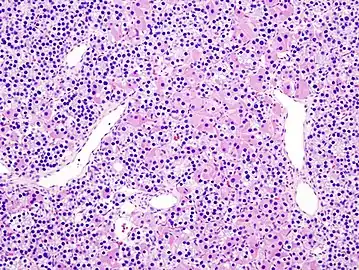

Histopatholgical image of parathyroid adenoma in a patient with primary hyperparathyroidism. Hematoxylin and eosin stain.

Histopatholgical image of parathyroid adenoma in a patient with primary hyperparathyroidism. Hematoxylin and eosin stain. Another view of the same lesion